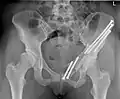

-

Schwere HD li.>re. vor der Operation -

Nach der Operation -

Skizze der Hüftdysplasie li. mit eingezeichneten Osteotomielinien -

Skizze der fertigen Triple-Osteotomie (rot gestrichelt: Verlauf der Beckenschrauben zur Fixierung)